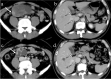

Gastrointestinal stromal tumors (GISTs) originating from the interstitial cells of Cajal in the muscularis propria are the most common mesenchymal tumor of the gastrointestinal tract. Multiple modalities, including computed tomography (CT), magnetic resonance imaging (MRI), fluorodeoxyglucose positron emission tomography, ultrasonography, digital subtraction angiography, and endoscopy, have been performed to evaluate GISTs. CT is most frequently used for diagnosis, staging, surveillance, and response monitoring during molecularly targeted therapy in clinical practice. The diagnosis of GISTs is sometimes challenging because of the diverse imaging findings, such as anatomical location (esophagus, stomach, duodenum, small bowel, colorectum, appendix, and peritoneum), growth pattern, and enhancement pattern as well as the presence of necrosis, calcification, ulceration, early venous return, and metastasis. Imaging findings of GISTs treated with antineoplastic agents are quite different from those of other neoplasms (e.g. adenocarcinomas) because only subtle changes in size are seen even in responsive lesions. Furthermore, the recurrence pattern of GISTs is different from that of other neoplasms. This review discusses the advantages and disadvantages of each imaging modality, describes imaging findings obtained before and after treatment, presents a few cases of complicated GISTs, and discusses recent investigations performed using CT and MRI to predict histological risk grade, gene mutations, and patient outcomes.